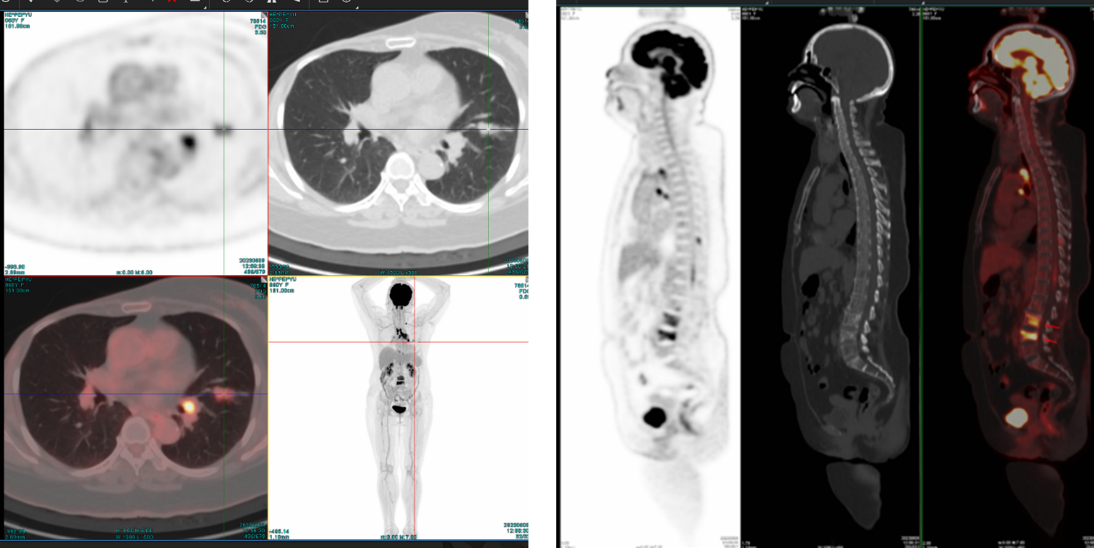

至2022年12月,患者CEA及CA15-3持续升高;2023年6月进一步检查提示疾病全面复发,DFS约60个月。PET/CT显示左肺上叶下舌段结节、区域多发肿大淋巴结以及胸腰椎多发骨质破坏,并伴糖代谢增高,提示肺、淋巴结及骨转移。